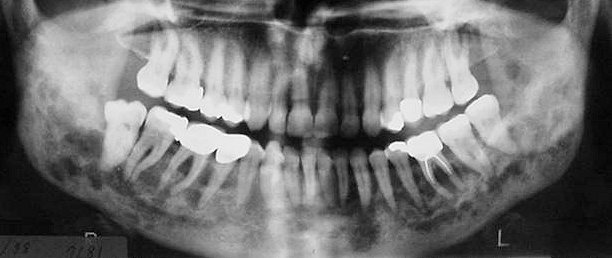

- Τις περισσότερες φορές οι βλάβες εντοπίζονται είτε ακρορριζικά είτε περιρριζικά των δοντιών δίνοντας την εικόνα περιακρορριζικών διαυγάσεων πολφικής αιτιολογίας ή περιοδοντικής νόσου.

- Οι αλλοιώσεις είναι διαυγαστικές με κάπως ανώμαλα ή σκοροφαγωμένα όρια και με τάση επέκτασης στους εν τω βάθει ιστούς. Με την υπολογιστική τομογραφία διαπιστώνεται διάτρηση και λύση των συμπαγών πετάλων ή του εδάφους του ιγμορείου άντρου και επέκταση των αλλοιώσεων στους παρακείμενους ιστούς. Σε σύντομο χρονικό διάστημα παρατηρείται απώλεια στήριξης των δοντιών και έντονη ευσειστότητα ή απόπτωση αυτών.